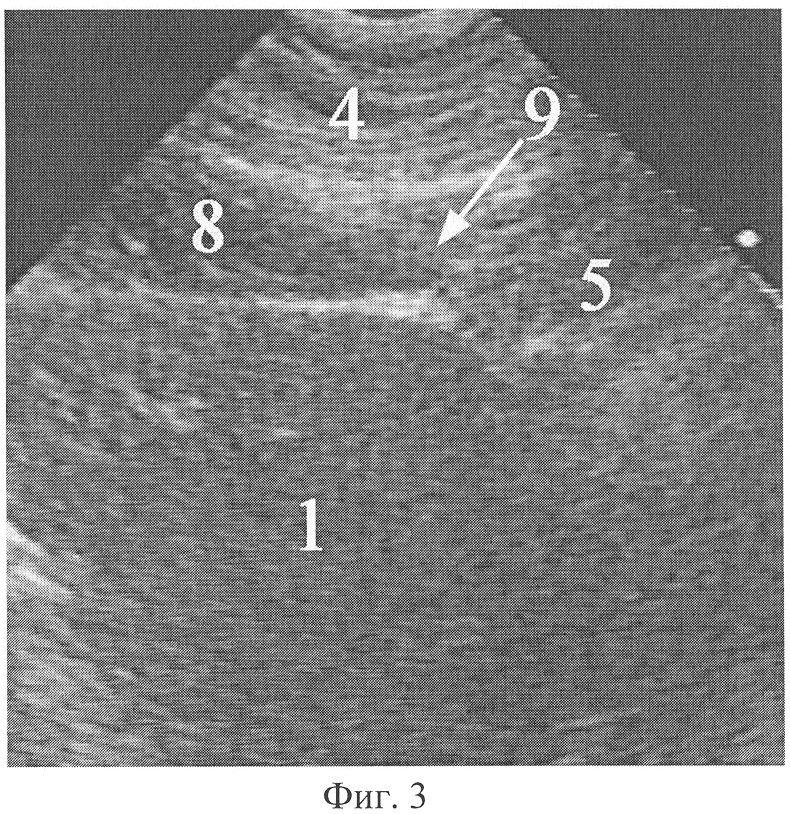

Фиг.3. Эхограмма сообщения абдоминомедиастинальной липомы с предбрюшинной жировой клетчаткой при продольном ультразвуковом сканировании из-под мечевидного отростка.

На фиг.3 обозначено: 1 – печень, 4 – мягкие ткани грудной стенки, 5 – абдоминомедиастинальная липома, 8 – предбрюшинная жировая клетчатка, 9 – сообщение абдоминомедиастинальной липомы с предбрюшинной жировой клетчаткой.